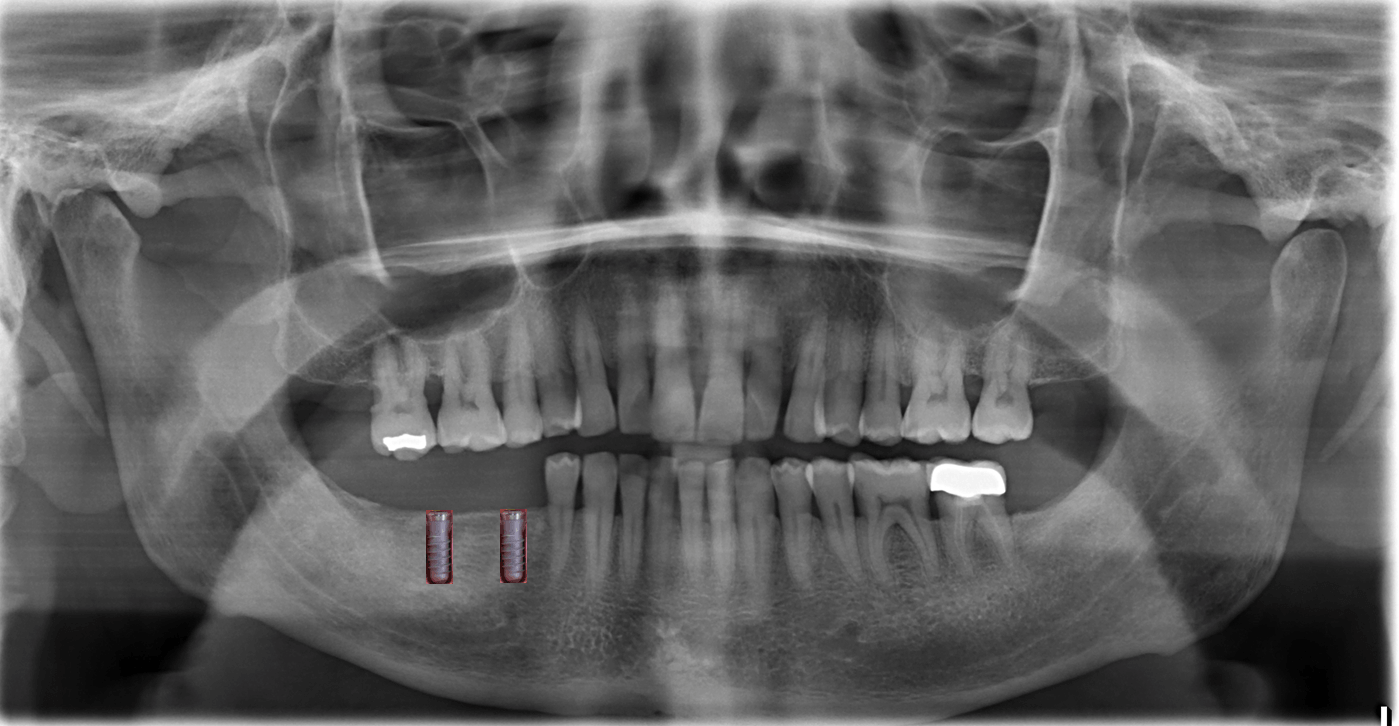

Röntgen, 3D und Untersuchung

Die Grundlage der endgültigen Planung

Implantate aus Titan und Keramik (zwei- oder dreiteilig).

Eine 3D Untersuchung "Digitale Volumentomographie" wird im DVT Zentrum Hamburg durchgeführt, Lerchenfeld 14, 22081 Hamburg, Tel 040-2269-4990. Sie geben Ihnen die CD mit, die wir dann hier einlesen.